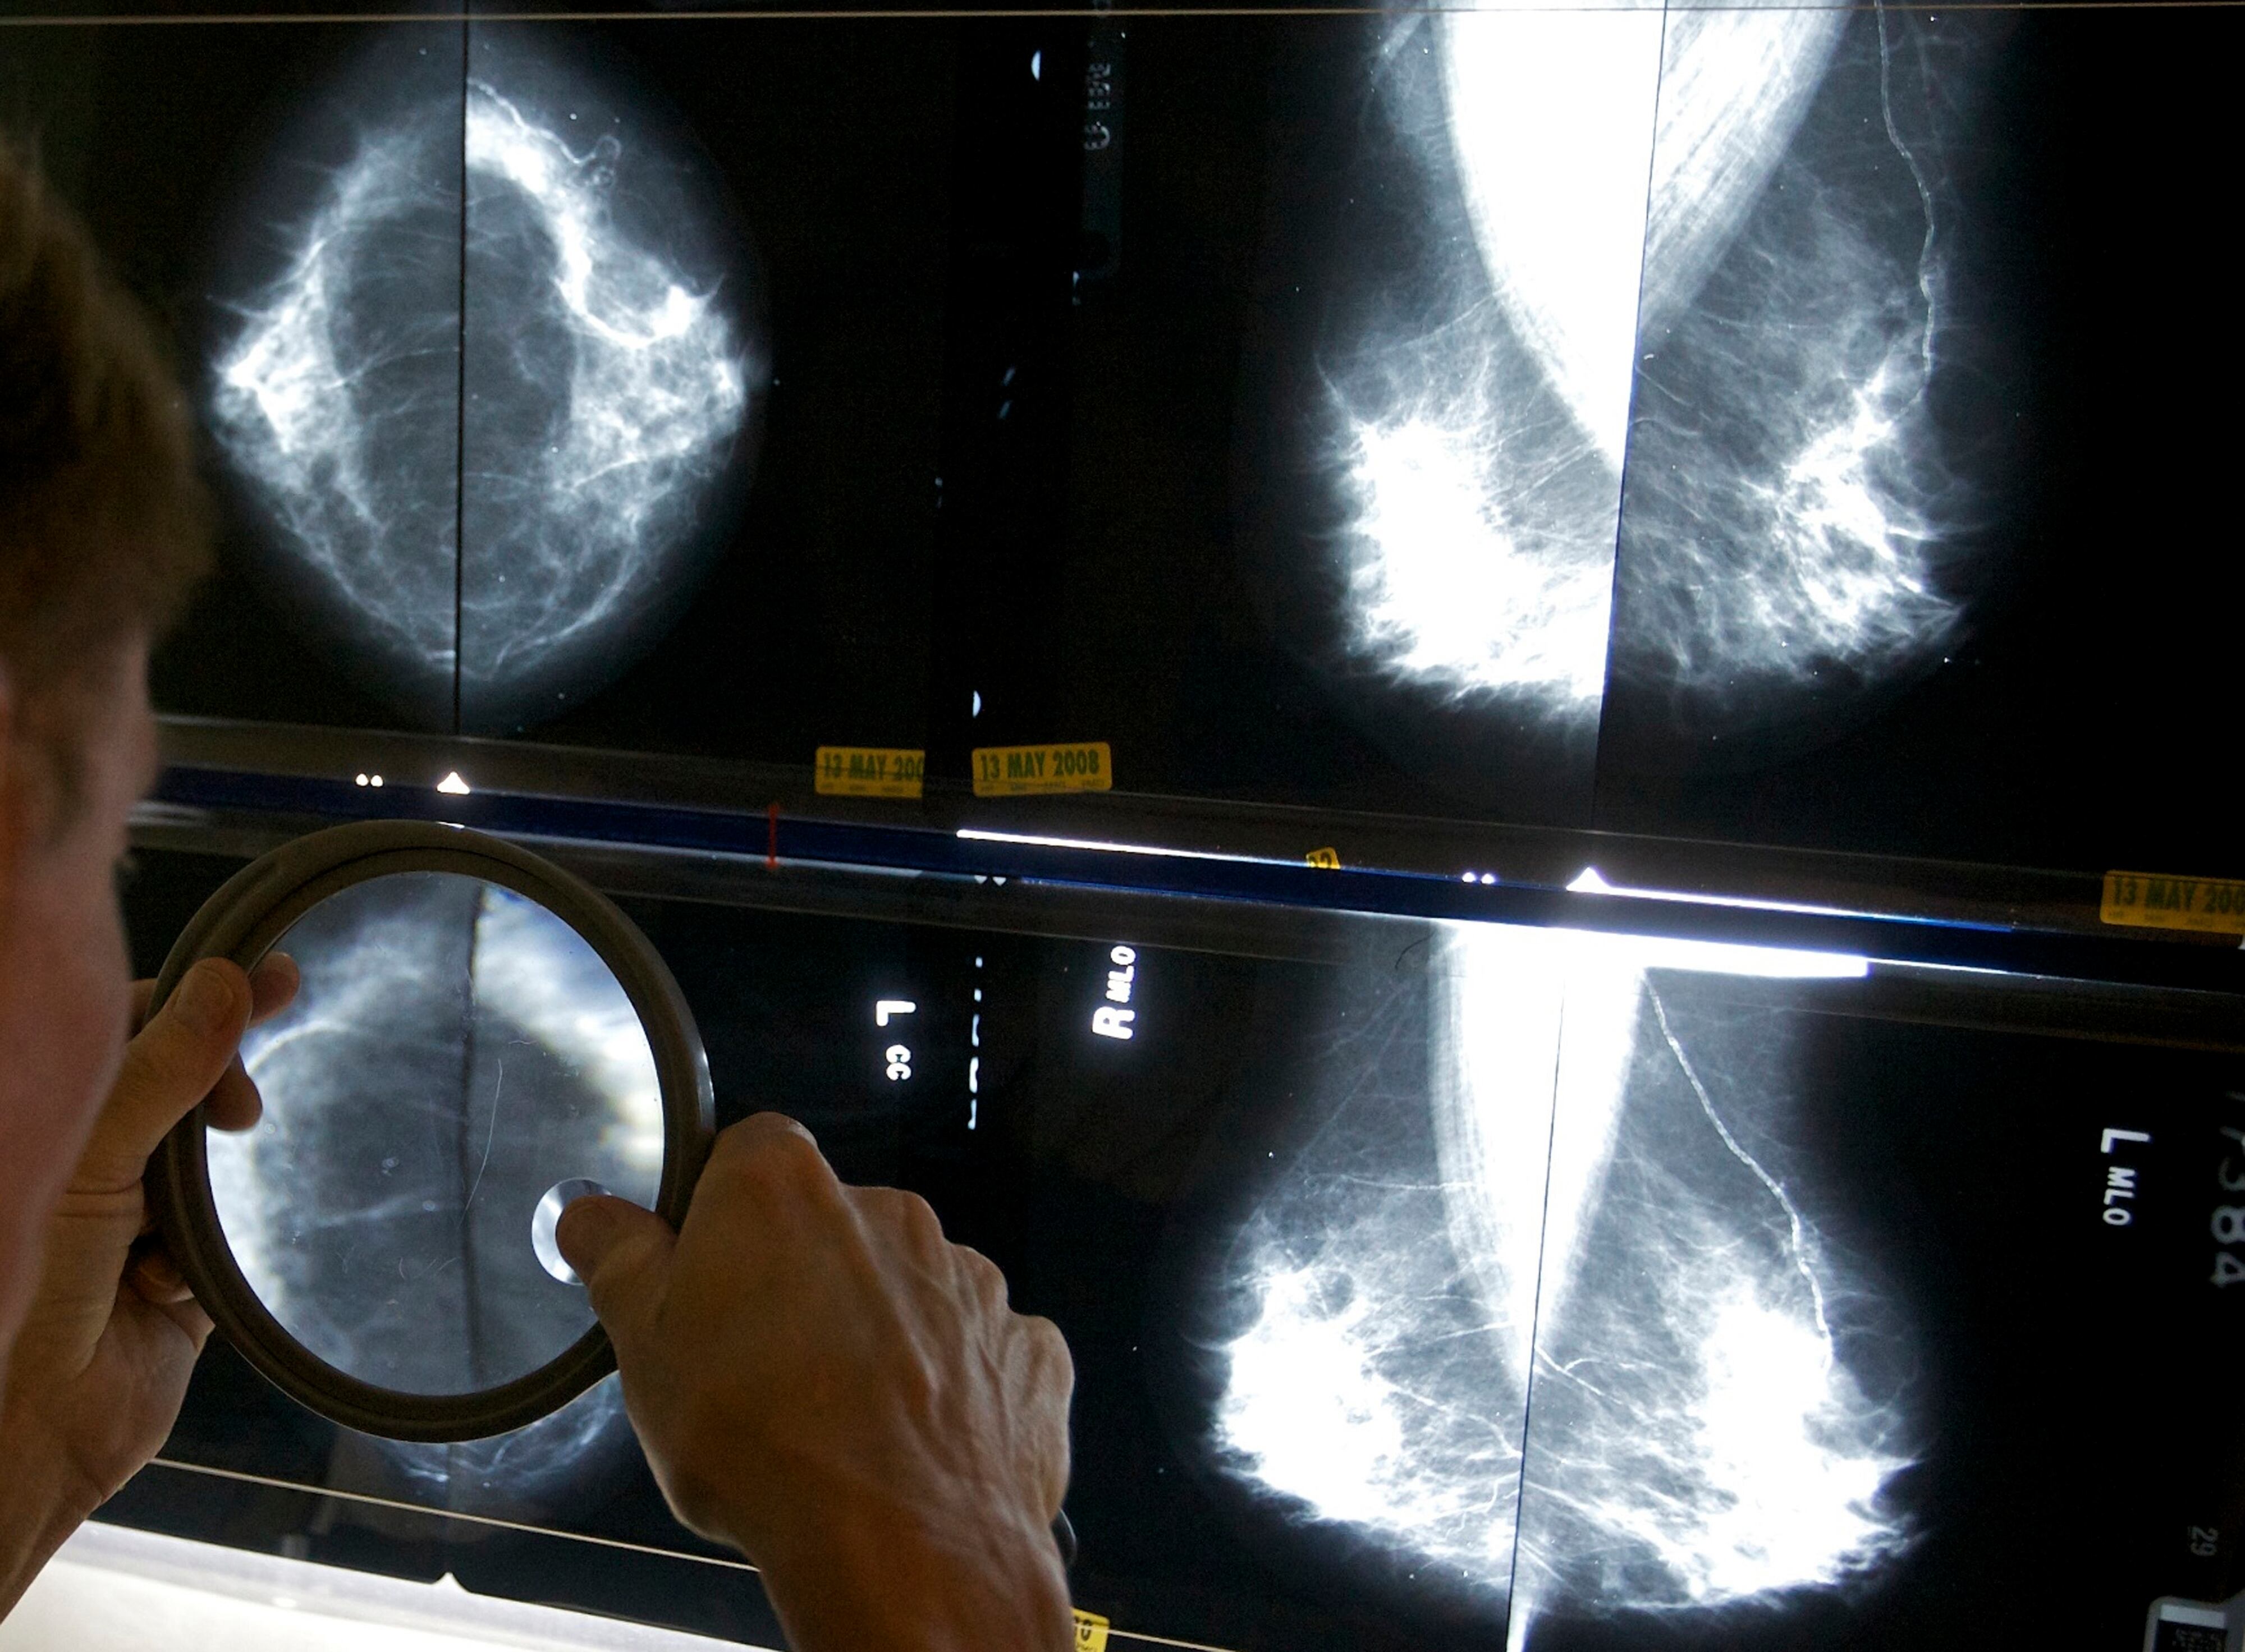

Cada año, unas 50.000 mujeres en Estados Unidos son diagnosticadas con carcinoma ductal in situ —o carcinoma intraductal—, en el que las células que recubren los conductos mamarios del seno se vuelven cancerosas, pero el tejido mamario cercano permanece sano. Muchas optan por someterse a cirugía, aunque no está claro si podrían en cambio adoptar un enfoque de “esperar y ver” bajo un monitoreo más frecuente.

El nuevo estudio, basado en dos años de datos, sugiere que tal monitoreo activo es una alternativa segura a la cirugía para muchas de estas mujeres, aunque algunos médicos querrán ver si los resultados se mantienen con el tiempo.

Entre las pacientes en el grupo de monitoreo, los cambios detectados en una mamografía provocarían una biopsia. También podrían optar por la cirugía en cualquier momento por cualquier motivo.